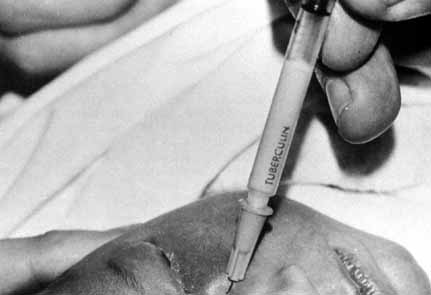

Fig. 23 Trauma to the inferior meatus and turbinate caused by difficulties in removing

a stiff stainless-steel type probe from the inferior meatus

with a hemostat. Fig. 23 Trauma to the inferior meatus and turbinate caused by difficulties in removing

a stiff stainless-steel type probe from the inferior meatus

with a hemostat.